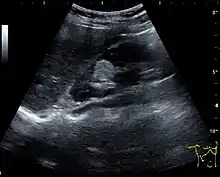

Figure 22. Chronic renal disease caused by glomerulonephritis with increased echogenicity and reduced cortical thickness. Measurement of kidney length on the US image is illustrated by ‘+’ and a dashed line.[1]

US is useful for diagnostic and prognostic purposes in chronic kidney disease. Whether the underlying pathologic change is glomerular sclerosis, tubular atrophy, interstitial fibrosis or inflammation, the result is often increased echogenicity of the cortex. The echogenicity of the kidney should be related to the echogenicity of either the liver or the spleen (Figure 22 and Figure 23). Moreover, decreased renal size and cortical thinning are also often seen and especially when disease progresses (Figure 24 and Figure 25). However, kidney size correlates to height, and short persons tend to have small kidneys; thus, kidney size as the only parameter is not reliable.[1]